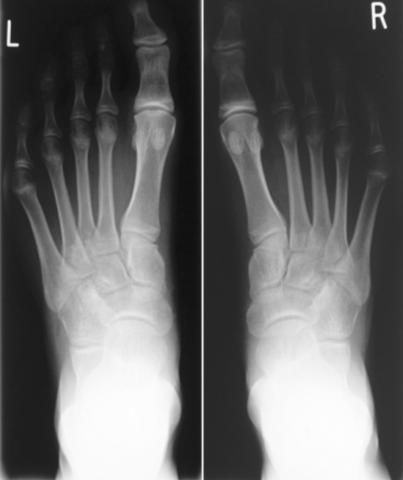

Radiographs of the feet showed findings consistent with

avascular necrosis, namely, flattening of the metatarsal heads

(being more pronounced on the left), with two small subchondral

cysts and dorsal osteophytes (Figures 1a&b). Haematological

investigations were normal. No further imaging was planned, as

the diagnosis was conclusive on the radiographs 1,2

Figure 1a Radiographs of both feet at presentation